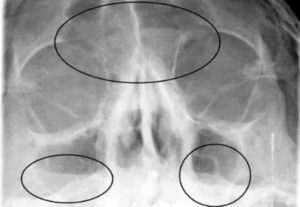

При гайморите носоподбородочная проекция рентген снимка покажет затемнение с верхним горизонтальным уровнем (скопившаяся жидкость визуализируется на темном фоне как контур светлого оттенка).

- Если болезнь в запущенной стадии, то затемнение будет расположено над носом, так как прогрессирующее воспаление переходит в лобные участки.

- Если темные участки обнаружены сразу в нескольких участках, то у пациента не только гайморит, но и фронтит.

Если в них есть жидкость (гной, кровь и др.), образуются затемнения (снижение пневматизации) с горизонтальной верхней границей.

| Экссудативный синусит | Выявляют затемнение в области синуса, в котором определяется горизонтальный уровень жидкости |

Рентгенограмма высокого качества позволяет без труда обнаружить утолщение слизистой оболочки носа, что указывает на наличие воспалительного процесса. Это характерный признай гайморита.

Если же на снимке виднеется жидкость, скопившаяся внутри пазух, позволяющая измерить ее объем, то опытный врач может «вычислить» и стадию патологии.

Затемнение (белые пятна) в пазухе носа на рентгене — первый признак патологического процесса, поэтому врачи внимание уделяют форме затемнения и его локализации.